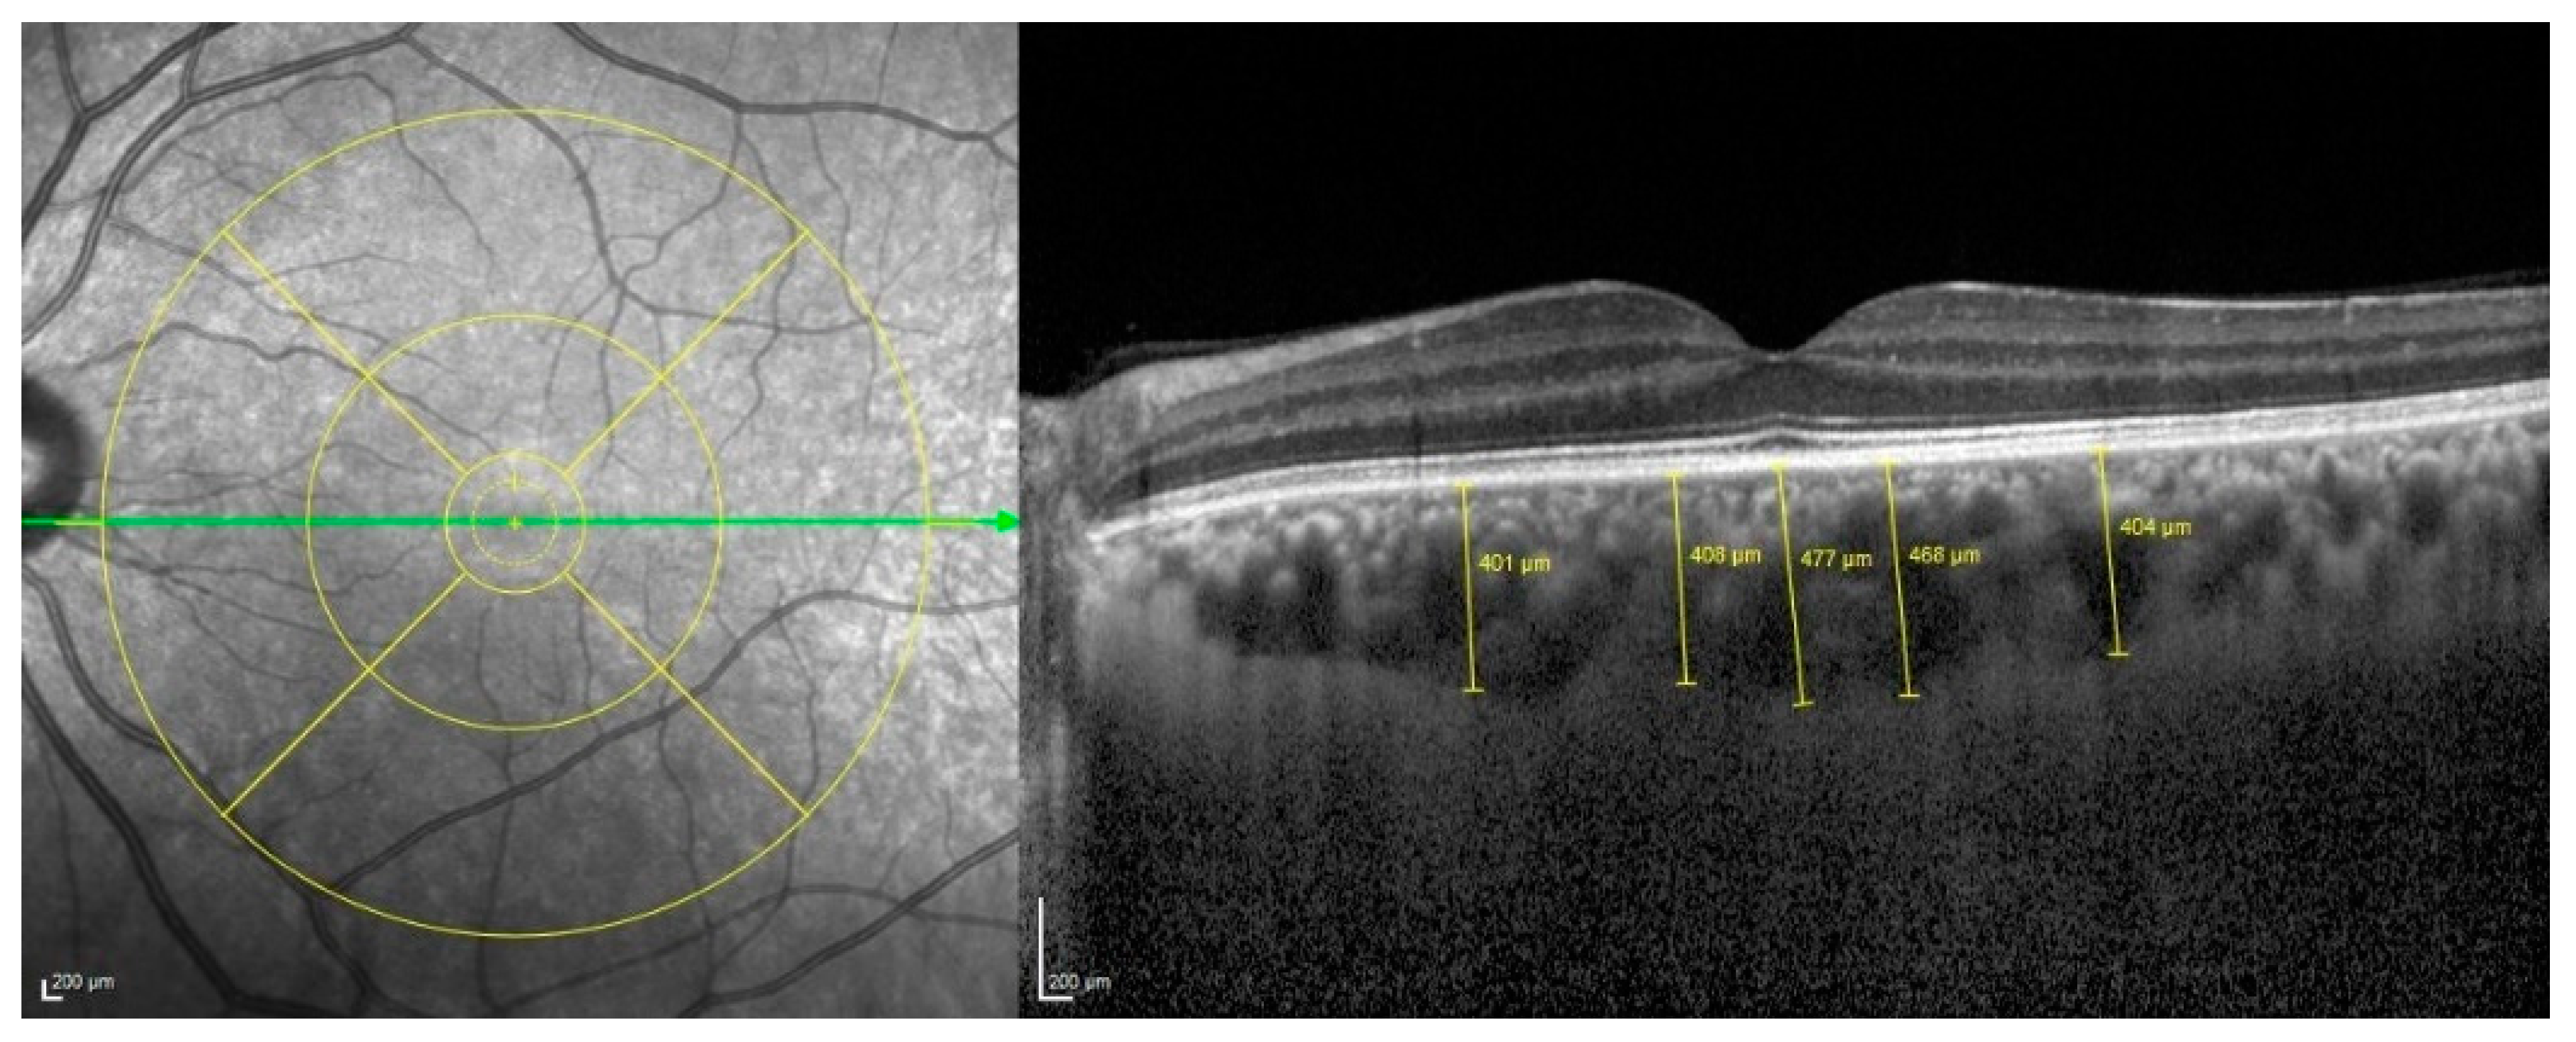

For the precise measurements of ChT, we utilized a high-fidelity precision caliper supplied by EDI-OCT, a renowned tool in ocular diagnostic imaging. This technique enabled a detailed assessment of the perpendicular distance between the hyperreflective outer border of the retinal pigment epithelium and the Bruch membrane layer. Measurements were carefully taken at five critical points along a horizontal scan line, directly at the subfoveal region, as well as at points 500 μm and 1500 μm both temporally and nasally from the fovea (Figure 2). To ensure the highest level of accuracy and consistency, if any single measurement demonstrated a deviation exceeding 10%, we promptly conducted a second round of measurements to verify the results and maintain data integrity.

In terms of ocular metrics, the mean subfoveal ChT was measured to be distinctly lower in the CAE cohort, registering at 297.88 ± 73.2 µm, compared to the control group’s average of 336.3 ± 94.4 µm. This difference in choroidal thickness is effectively illustrated in Figure 1, which depicts measurements taken at five different locations along the retina, underscoring the variations in structural health between the two groups. A significant difference was observed in ChT at 500 µm nasal and temporal area. The choroid was significantly thinner at these locations in the CAE group (p < 0.05) (Table 2).

Figure 2. These pictures show choroidal thicknesses obtained at 5 different points (subfoveal, nasal 500 µm, temporal 500 µm, nasal 1500 µm, temporal 1500 µm).